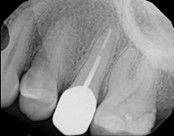

Apicoectomy:

Before, the failed root canal

Immediately after the microsuregery

3-months after shows complete healingThe patient was told by a specialist that the root canal failed, the only option was extraction and an implant. She did not want to do that; she wanted to keep her tooth, after all, it is her front tooth. She found us. We performed an apical microsurgery with the laser. The tooth was saved and is still functioning. This is a poor area for an implant, so much better to save the tooth.